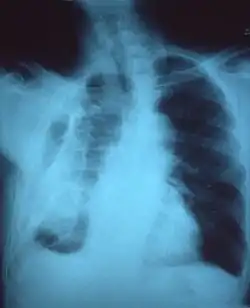

تليف صدري

التليف الصدري هو تليف الفراغ الجنبي المحيط بـ الرئتين .[1][2] ويمكن أن يكون له عدة أسباب بما في ذلك الانصباب الجنبي ، الصدر المدمى ، و السل.

![]() Fibrothorax on chest x-ray Fibrothorax on chest x-ray | |